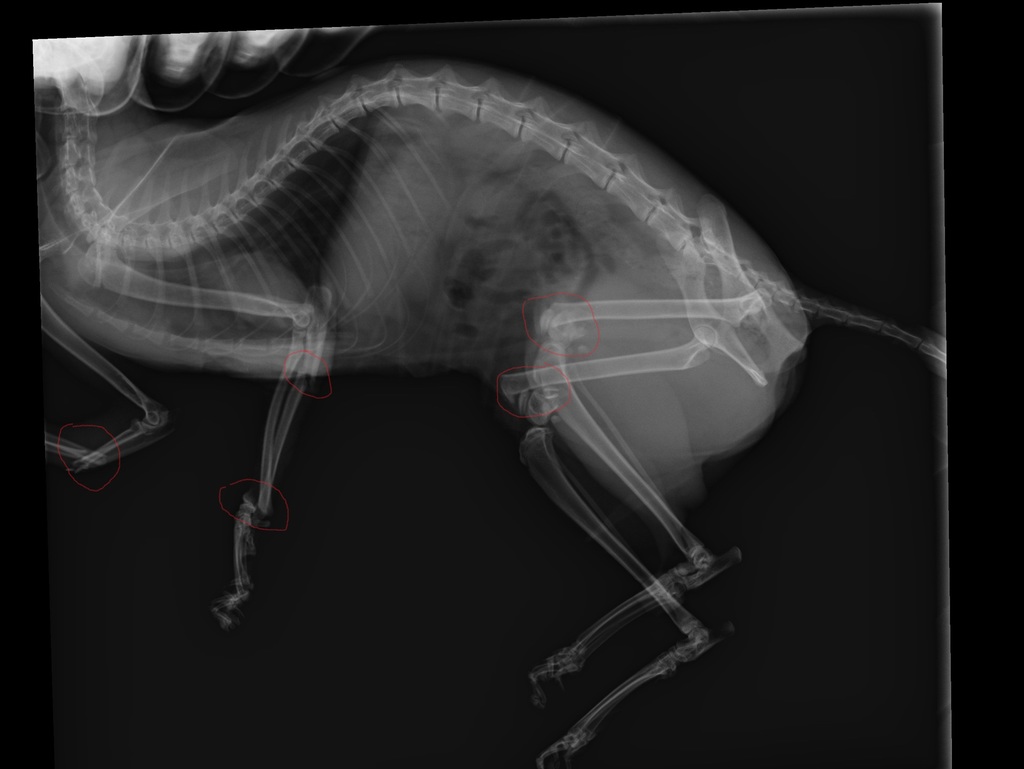

Рентгеновские снимки анатомии собак: строение и здоровье